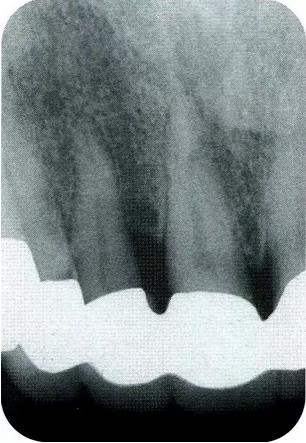

▼圖13-7,8 術(shù)前與術(shù)后8個月的x片。牙槽骨明顯改善。